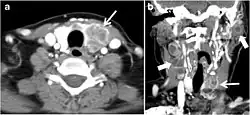

Fig. 7. A 51-year-old female patient post total thyroidectomy for PTC with elevated thyroglobulin measurement. an Axial non-enhanced CT scan of the neck at the level of the thyroid bed demonstrates a well-defined, rounded, homogenously dense soft tissue situated between the trachea and left internal jugular vein (white arrow). b Transverse ultrasound image of the neck demonstrates a well-defined, homogeneous, hypoechoic soft tissue nodule measuring 6 mm (white arrow) with no detected micro-calcifications. Biopsy showed a predominantly residual normal thyroid tissue with micro-foci of PTC.[1] -

Fig. 8. A 48-year-old male patient post total thyroidectomy with PTC recurrence. a Transverse greyscale ultrasound of the neck demonstrates a left thyroid bed heterogeneous, predominantly hypoechoic irregular lesion with calcifications (white arrow). b A spot image of iodine 123 total body scan of the neck demonstrate a focus of abnormal radiotracer uptake at the left thyroid bed (Black arrows) between the annotated markers. c Enhanced axial CT scan of the neck demonstrates an enhancing large left thyroid bed mass (white arrow) with no calcifications. The lesion exerts a mass effect on the oesophagus (black arrow) and is inseparable from the trachea.[1] -

Fig. 9. A 58-year-old male patient with persistence PTC at thyroid bed with hypervascular nodal metastasis. a–c Transverse greyscale and colour Doppler neck ultrasound demonstrate hypoehoic soft tissue in the left thyroid bed (white arrow in a). There are a heterogeneous enlarged lymph nodes at level 2 and 3 with markedly increased vascularity (white arrow in b and c). d–f Enhanced axial CT images of the neck demonstrate a 2.7 × 1.4 cm hypodense soft tissue lesion anterior to the left carotid sheath (white arrow). There are left-sided enhancing abnormal and enlarged lymph nodes at cervical level 2 and 3 (black arrows).[1]